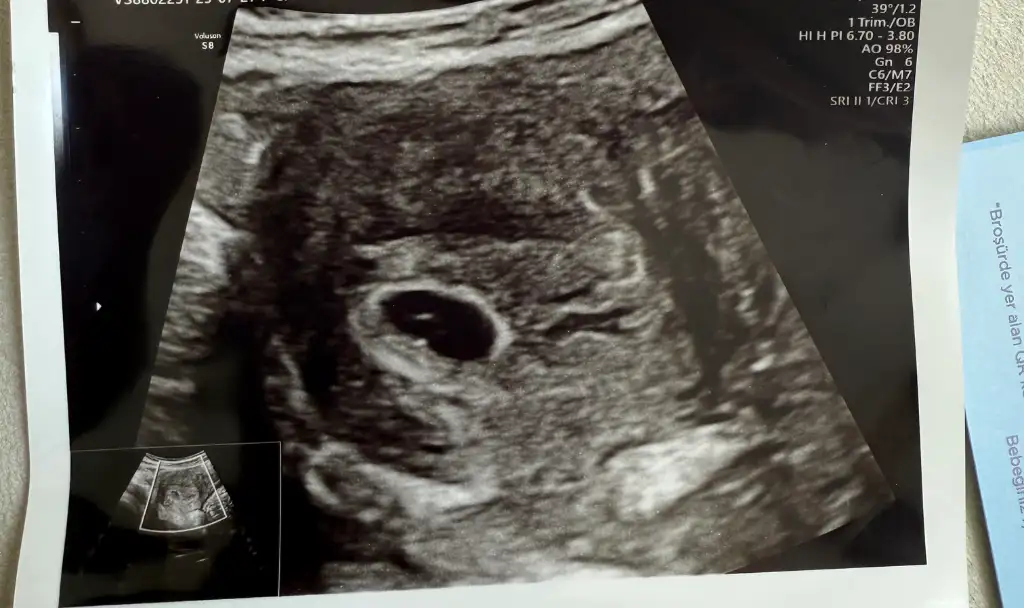

Canım hiç morelini bozma benimkinde öyleydi şuan 9 haftalık olması gerekirken doktora göre 8 haftalık şuanKızlar ben sımdı doktordan cıktım sata göre 6 haftalık olması gereken bebek 4+2 çıktı keseyi vs gördük olması gerektiği gibi dedi ama benım anlamsız bi şekilde morelım bozuldu